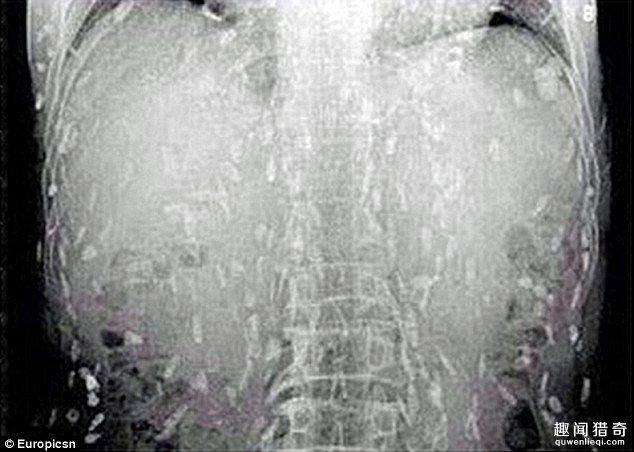

相信不少人都非常喜歡吃生魚片,近日,一名男子卻因為過度食用生魚片而差點喪命。 據報道,這名男子因為腹痛和皮膚瘙癢而前去醫院就診,在X光下顯示了這駭人的一幕。

這名男子的身上已經全是寄生蟲,看了讓人頭皮發麻。 醫生認為他是因為吃了太多的生魚片,才會有如此嚴重的感染。 目前他正轉往廣州市第八人民醫院接受治療。